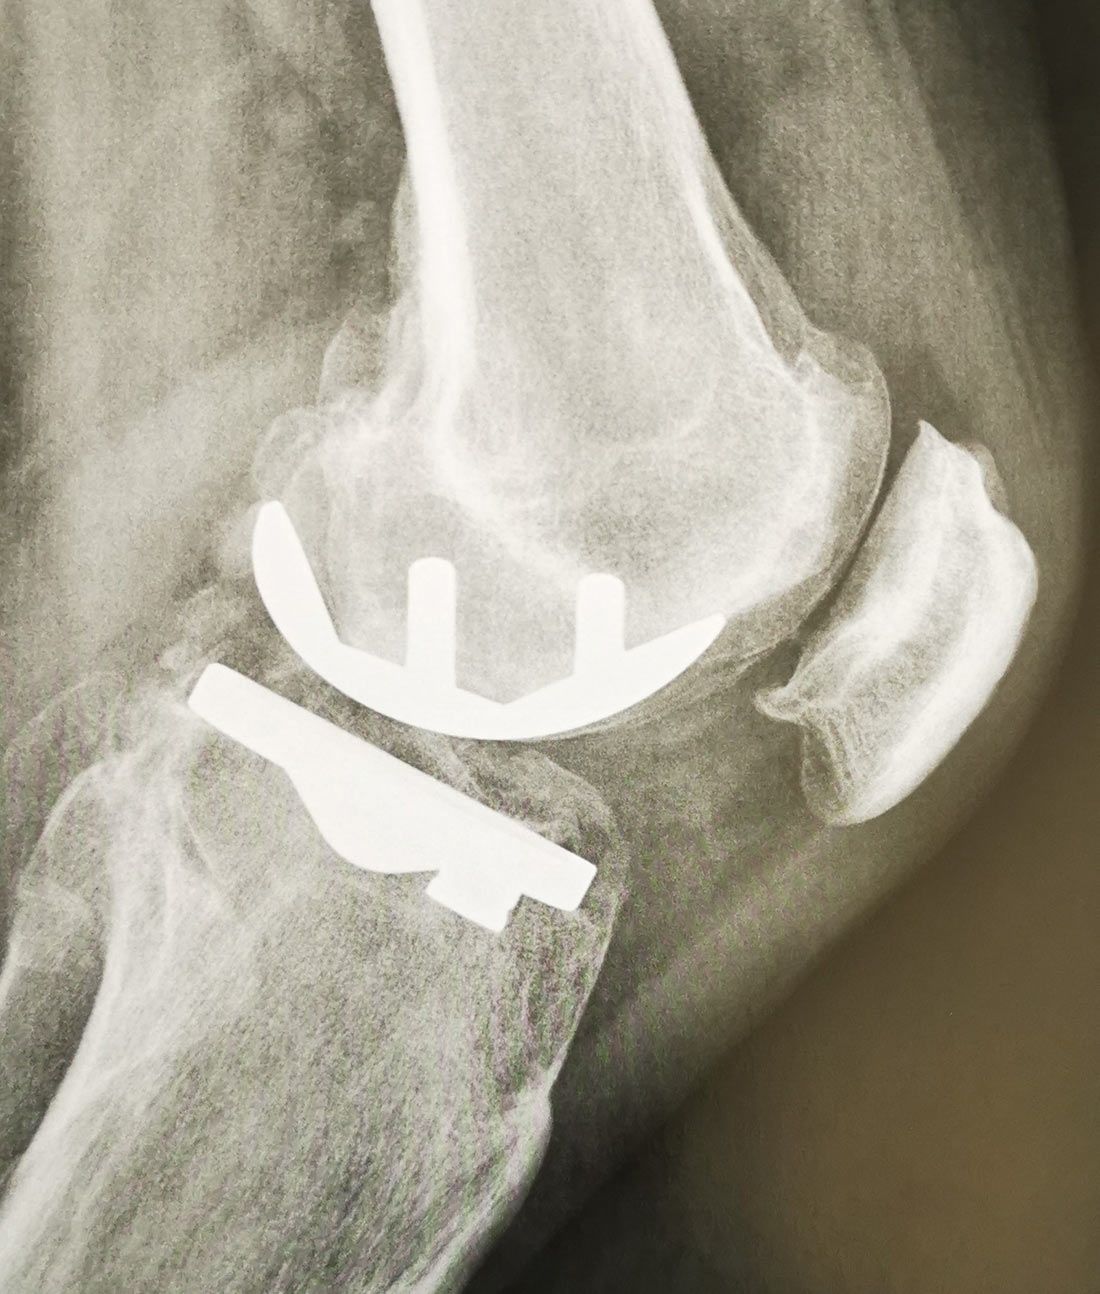

Les Prothèses Totales du Genou (PTG)

Quand l’arthrose atteint tout le genou, c’est la seule option envisageable. Les prothèses de genou vont remplacer les surfaces articulaires du genou.

On les appelle également prothèses tricompartimentales de genou, car elles remplacent les 3 compartiments du genou :

- Compartiment interne/médial ;

- Compartiment externe/latéral ;

- Compartiment fémoro-patellaire (rotulien).